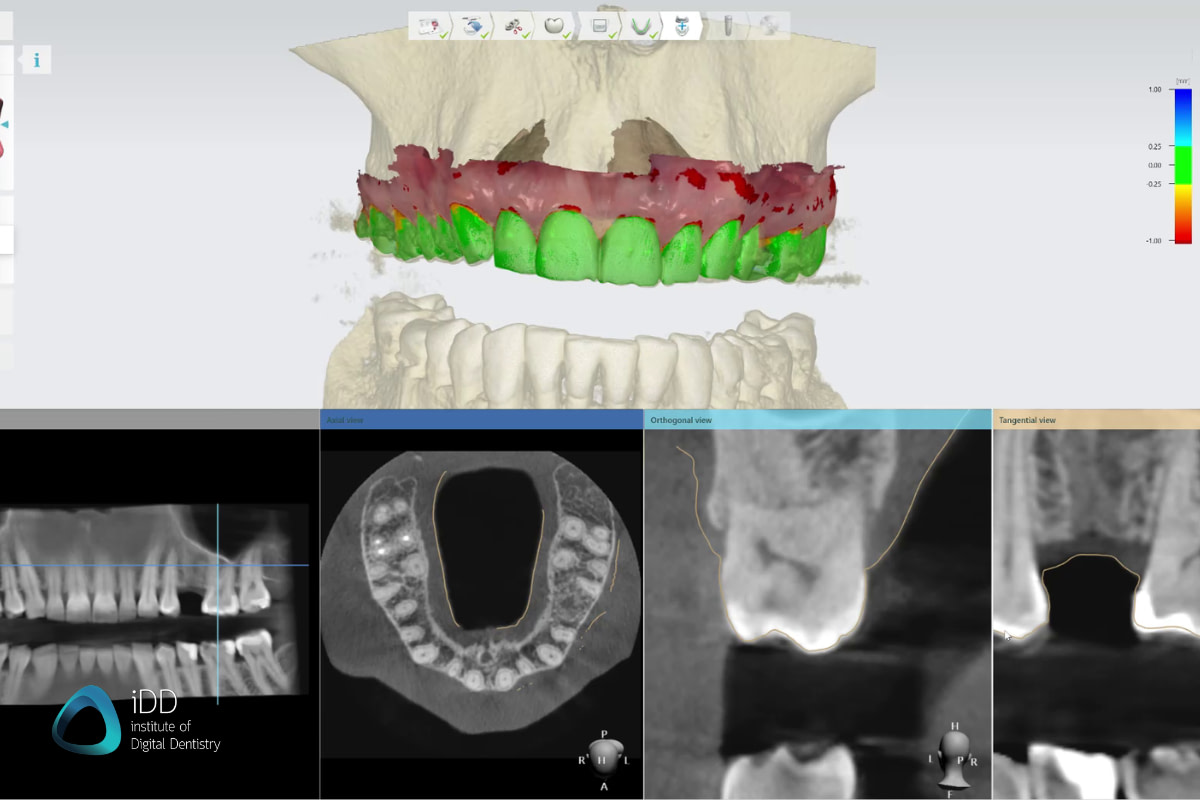

3. Workflow Integration: Beyond DICOM Export

True efficiency gains come from eliminating manual data handling. 2026 leaders implement:

Digital Workflow Integration

Digital Dentistry Technical Review 2026: CBCT Integration Framework

The CBCT Integration Imperative: Beyond Image Acquisition

In 2026, the “best dental CBCT” is no longer defined by resolution alone (though ≤75μm isotropic remains clinical baseline). It is measured by integration velocity – the system’s ability to inject actionable 3D data into production pipelines with zero manual intervention. Modern workflows demand CBCT systems functioning as data origination nodes within closed-loop digital ecosystems, not isolated imaging devices.

Workflow Integration Architecture

CAD Software Compatibility: The Interoperability Reality Check

Clinical utility hinges on seamless data translation. Not all DICOM implementations are equal – critical factors include:

- Metadata Preservation: Transfer of FOV, kVp, mA, and reconstruction parameters

- Segmentation Layer Support: Natively importable tissue-specific masks

- Coordinate System Alignment: Precise spatial registration with intraoral scans